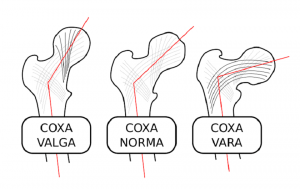

می 10, 2020کوکسا والگا یا برون خمیدگی لگن نوعی بدشکلی در مفصل هیپ است که زاویه ایجاد شده بین سر استخوان فمور و تنه آن افزایش می یابد، که معمولا به بالای ۱۳۵ درجه می رسد.

این بدشکلی معمولا با کاهش زوایای استابولوم و نیمه دررفتگی سر استخوان فمور همراه است.

کوکسا والگا زمانی رخ می دهد که زاویه بین گردن وشفت فمور افزایش پیدا کند ( که به این زاویه، زاویه inclination فمور یا زاویه caput-collum-diaphyseal (CCD) گفته می شود).

مقدار نرمال آن در بزرگسالان ۱۳۵-۱۲۵ درجه است که در هنگام تولد ۲۵-۲۰ درجه و در بچه ها ۱۰ درجه از این مقدار بیشتر است.